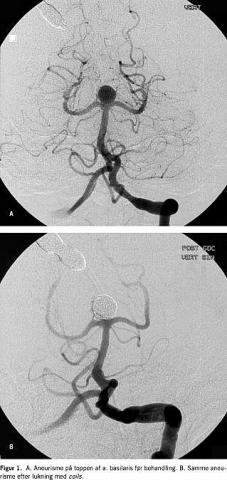

Subaraknoidalblødning fra et bristet cerebralt aneurisme rammer i Danmark årligt ca. 500 personer og viser sig hyppigst ved pludseligt indsættende, voldsom hovedpine. Ca. 30% dør umiddelbart. Ubehandlet vil ca. 50% af de overlevende få en reblødning inden for de første seks måneder. Den bedste metode til at forebygge dette er endovaskulær lukning af aneurismet. Metoden blev introduceret i 1990 af Guido Guglielmi. Gennem et mikrokateter placeret i aneurismet oplægges platinspiraler (coils) til aneurismesækken er fyldt op (Figur 1 ). I International Subarachnoid Aneurysm Trial ((ISAT), som er et randomiseret studie, har man fastslået, at coil- behandling giver signifikant bedre slutresultat end kirurgi i de tilfælde, hvor begge behandlinger er mulige [1]. I dag er flere end 125.000 patienter verden over blevet behandlet med coil, og tiårsresultaterne er tilgængelige [2]. Mindst 75% af alle aneurismer kan lukkes endovaskulært med lav komplikationsfrekvens. Det forventes, at denne del stiger i takt med udviklingen af nye teknikker [3].